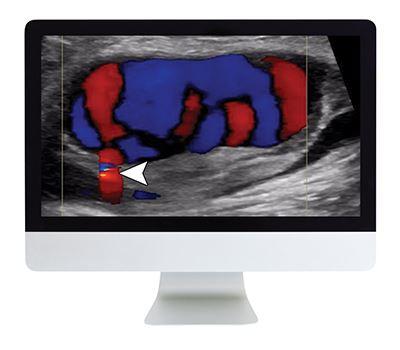

- Vascular—S. Bhatt

- Doppler Artifact—D. Rubens (didactic lecture)

- Vascular—D. Rubens and S. Bhatt

- Waveform Recognition in Carotid Doppler—S. Bhatt (didactic lecture)

- Vascular Ultrasound—C. Deurdulia

- Pearls and Pitfalls of Carotid Doppler—C. Deurdulian (didactic lecture)